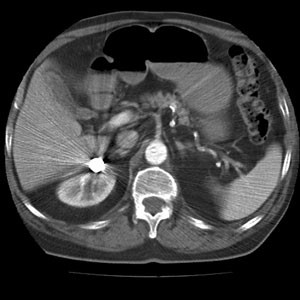

Fig. 3.